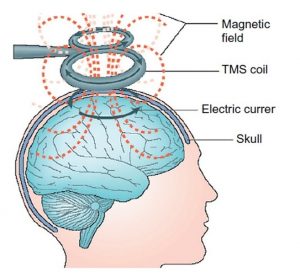

امواج مغناطیسی که دستگاه TMS تولید می کند از پوست و مو و استخوانهای جمجمه عبور می کند وارد مغز می شود و پس از برخورد با سطح قشری مغز به امواج الکتریکی تبدیل می شود این جریان های الکتریکی بر سلول های مغز اثر می گذارد و باعث انتشار انتقال دهنده های عصبی مانند سروتونین، نور اپی نفرین و دوپامین می شوند.

در واقع TMS به ما امکان برقراری ارتباط مستقیم با نورون های موجود در مغز را به زبان خودشان (الکتریسیته) می دهد. فرکانس و مدت زمان امواج توسط دستگاه TMS قابل کنترل است. بسیار مهم است که TMS نقطه ی مناسبی را در مغز شما هدف قرار دهد در غیر این صورت ممکن است منافعی را که واقعا به آن احتیاج دارید، دریافت نکنید.